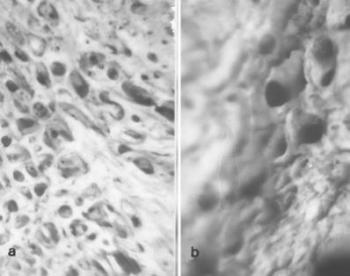

70. ábra. a) A 69. képen bemutatott csontdefektus alapján sűrű gerendázatú spongiosa b) A csontelváltozás peremén fonatos, scleroticus csontszerkezet figyelhető meg Sztereómikroszkópos felvétel a) 40×, b) 100× nagyítás

Daganatszerű léziók kialakulhatnak fejlődési zavar, csíraszóródás következtében, (csonton belüli synoviális cysták, ganglionok), lehetnek ismeretlen eredetű sarjadzások, amint a histiocytosis X néven összefoglalt három kórkép (Letterer-Siwe kór, Hand-Schüller-Christian kór és eosinophil granuloma), néha körülírt csontosodási defectus (fibrosis cystica localisata, fibroma non ossificans) utánozza a daganatot. A röntgen- és CT-képen felritkulás, vagy cystaképződés, környezetében scleroticus szegély, periostealis felrakódás észlelhető, a hisztológiai vizsgálat nem ad támpontot. A paleopathologusnak az életkor, a lokalizáció, másodlagos csontelváltozások, a finom rtg-jelek alapján kell állást foglalnia, de a diagnózis így is bizonytalan. Esetünk: az 5–7 éves gyermek, akinek bal homlokcsontján, a torus supraorbitalis fölött ovális, 35x30 mm átmérőjű defektus látszott (69. ábra, 70. ábra). A felső peremen 1–2 mm magasságú sarkantyú-képződés, alsó szélénél a csontfelület sima. A rtg-felvételen élesszélű, alapján scleroticus, a lamina externára és diploera kiterjedő csonthiány, a mikroszkópos képben a széleken apró csontüregek, a diploe szerkezeti átépülése, az állomány tömörülése mutatkozott. Legmélyebb pontján, az orbitához közelebb eső területen a lamina internán 2x1 és 4x1 mm-es élesszélü perforációs nyílások, környezetükben vaskos, fonatos csontképződéssel. Az intracranialis oldalon eltérés nem volt. A radiológiai és mikromorfológiai kép alapján az epidermoid cysta, a haemangioma (Capasso és mtsai 1991, Gladykowska-Rzeczycka 1982), és osteoclastoma (Köhler és Zimmer 1982) lehetősége elvethető, ám igen hasonló Strouhal (1976/77) eseteihez, akiken a homlok és falcsonton ugyanilyen képet észlelt, mindkettőt Hand-Schüller-Christian kórnak tartotta. Diagnosisunk: Histiocytosis X, amely főként gyermek és ifjúkorban, a koponyacsontokon szokott jelentkezni.